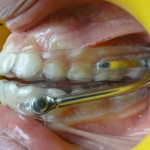

L’appareil est fait d’un système de gouttières et d’activateurs : ce sont les bielles présentes de chaque côté.

Vue de Gauche